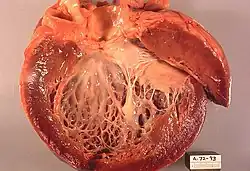

![]() Obraz sekcyjny serca w kardiomiopatii rozstrzeniowej | |

Kardiomiopatia rozstrzeniowa (łac. cardiomyopathia dilatativa), kardiomiopatia zastoinowa (łac. cardiomyopathia congestiva), kardiomiopatia przekrwienna – choroba mięśnia sercowego polegająca na jego ścieńczeniu, zwłaszcza w obrębie komór. Następuje wybiórcze powiększenie jąder kardiomiocytów bez przerostu komórki oraz zwłóknienie śródmiąższowe i okołonaczyniowe. Podobny obraz można spotkać w kardiomiopatii wtórnej, czyli na tle zapalenia mięśnia sercowego, co utrudnia postawienie właściwej diagnozy. Kardiomiopatia rozstrzeniowa powoduje zmniejszenie kurczliwości serca, co prowadzi najpierw do powstania lewokomorowej niewydolności tego mięśnia, a następnie do jego niewydolności obukomorowej. Rozstrzeń dotyka często także oba przedsionki. Przerost jest z reguły asymetryczny.